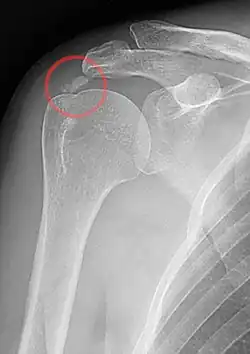

A plain X ray of the shoulder showing calcific tendinitis

Calcific tendinitis is a common condition where deposits of calcium phosphate form in a tendon, sometimes causing pain at the affected site. Deposits can occur in several places in the body, but are by far most common in the rotator cuff of the shoulder. Around 80% of those with deposits experience symptoms, typically chronic pain during certain shoulder movements, or sharp acute pain that worsens at night. Calcific tendinitis is typically diagnosed by physical exam and X-ray imaging. The disease often resolves completely on its own, but is typically treated with non-steroidal anti-inflammatory drugs to relieve pain, rest and physical therapy to promote healing, and in some cases various procedures to breakdown and/or remove the calcium deposits.

Calcific tendinitis is typically diagnosed by physical examination and X-ray imaging.[1] During the formative phase, X-ray images typically reveal calcium deposits with uniform density and a clear margin.[1] In the more painful resorptive phase, deposits instead appear cloudy and with unclear margins.[1] By arthroscopy, formative stage deposits appear crystalline and chalk-like, while resorptive stage deposits appear smooth resembling toothpaste.[1] Ultrasound is also used to locate and assess calcium deposits. In the formative stage, deposits are hyperechoic and arc-shaped; in the resorptive stage deposits are less echogenic and appear fragmented.[1][3]